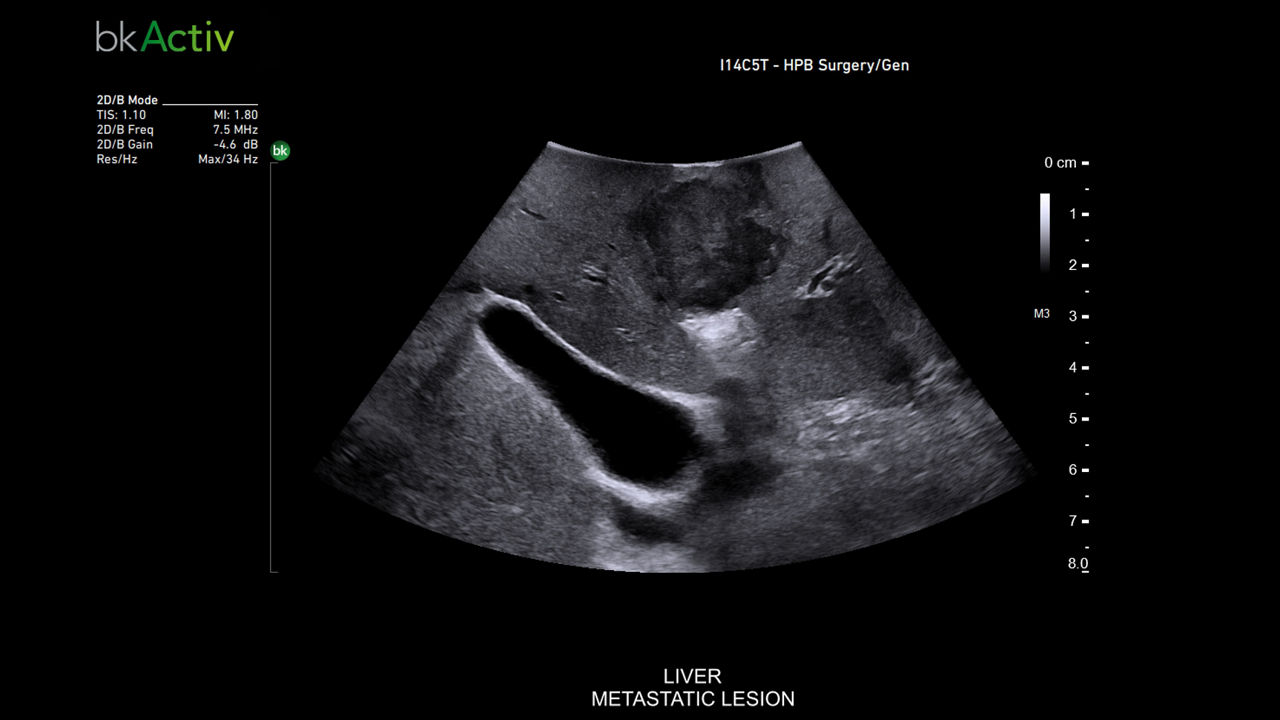

General surgery

Intraoperative ultrasound systems aid urinary tract procedures like cystoscopy and nephrolithotomy, improving visualization, accuracy, and surgical outcomes.

bkActiv Ultrasound System

The bkActiv ultrasound system offers advanced imaging for neurosurgery, urology, colorectal, and pelvic floor procedures. With enhanced resolution, customizable UI, and flexible monitor, it ensures precise, real-time guidance and improved surgical outcomes.